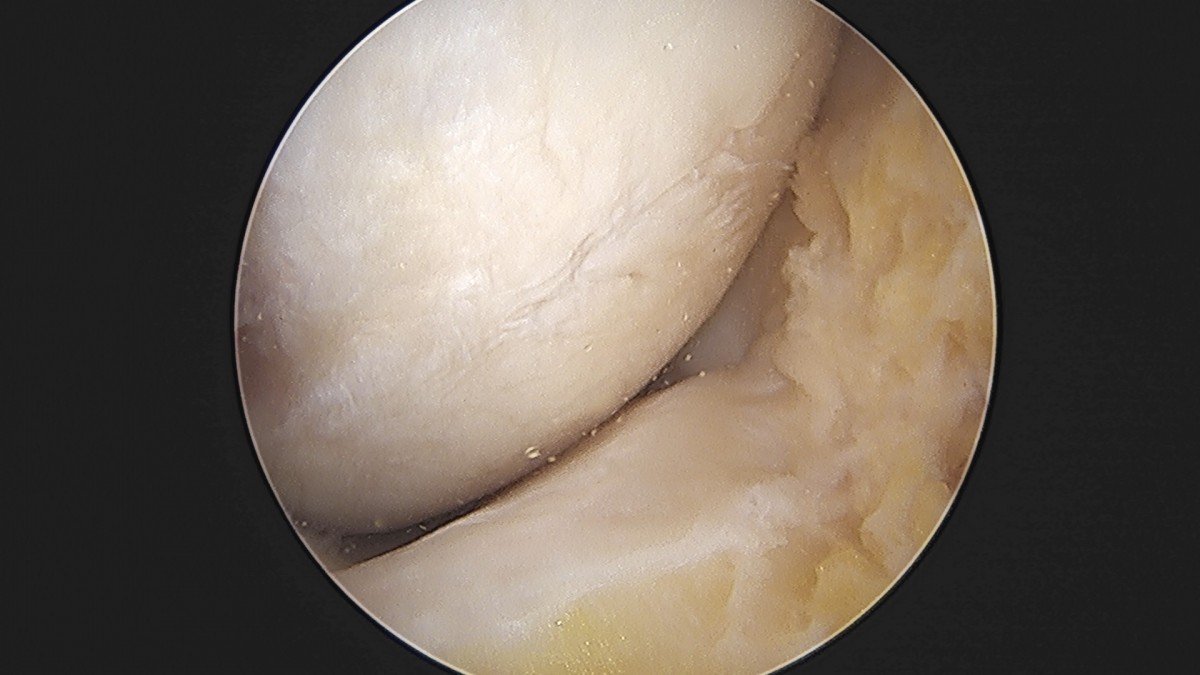

이재상원장님 무릎 반월상 연골판 절제술 박강O 환자

작성자 최고관리자 댓글 0건 조회 381회 작성일 25-09-16 15:47